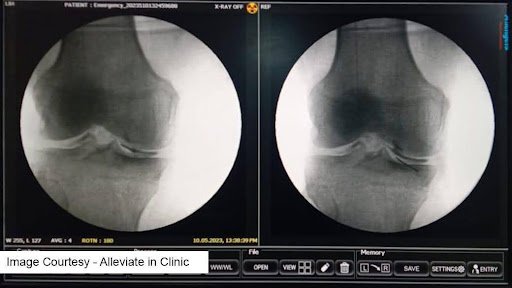

Weight bearing AP view X ray knee showing Grade 3 Knee Osteoarthritis. Regenerative injection treatments are attempted only till Grade 3 Stage of the disease.

Knee osteoarthritis (OA) is a progressive condition where cartilage slowly breaks down, leading to stiffness, pain, and loss of mobility. The Kellgren-Lawrence (KL) grading system defines early OA as:

- Grade 1: Minimal joint changes, doubtful narrowing

- Grade 2: Definite narrowing with osteophytes

- Grade 3: Moderate narrowing, frequent pain and stiffness

At these stages, cartilage is still present—making regenerative therapies most effective.